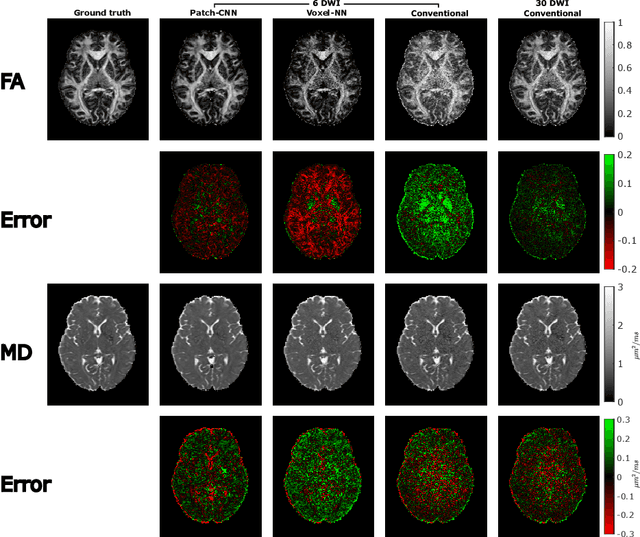

We propose a new method, Patch-CNN, for diffusion tensor (DT) estimation from only six-direction diffusion weighted images (DWI). Deep learning-based methods have been recently proposed for dMRI parameter estimation, using either voxel-wise fully-connected neural networks (FCN) or image-wise convolutional neural networks (CNN). In the acute clinical context -- where pressure of time limits the number of imaged directions to a minimum -- existing approaches either require an infeasible number of training images volumes (image-wise CNNs), or do not estimate the fibre orientations (voxel-wise FCNs) required for tractogram estimation. To overcome these limitations, we propose Patch-CNN, a neural network with a minimal (non-voxel-wise) convolutional kernel (3$\times$3$\times$3). Compared with voxel-wise FCNs, this has the advantage of allowing the network to leverage local anatomical information. Compared with image-wise CNNs, the minimal kernel vastly reduces training data demand. Evaluated against both conventional model fitting and a voxel-wise FCN, Patch-CNN, trained with a single subject is shown to improve the estimation of both scalar dMRI parameters and fibre orientation from six-direction DWIs. The improved fibre orientation estimation is shown to produce improved tractogram.